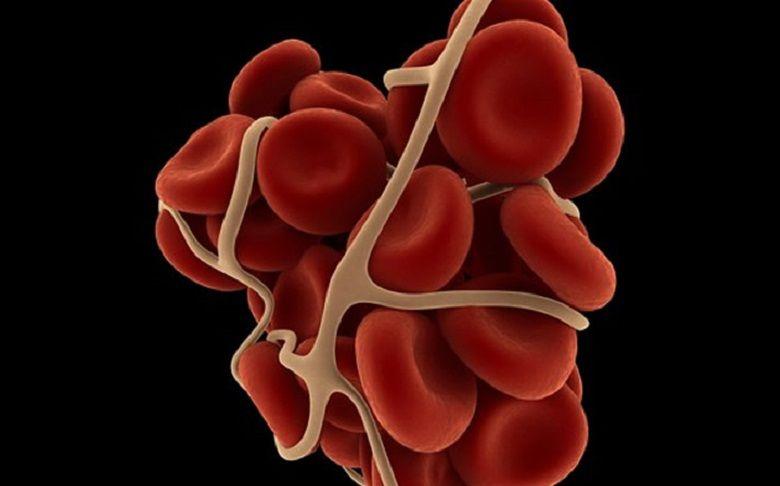

Mielofibrosis: una enfermedad silenciosa, veloz y que afecta cada vez a más jóvenes

El 26 de noviembre se conmemora el Día de la Mielofibrosis, una fecha para concientizar sobre esta enfermedad que no manifiesta síntomas tempranamente y se desarrolla rápidamente sobre el organismo.

La...